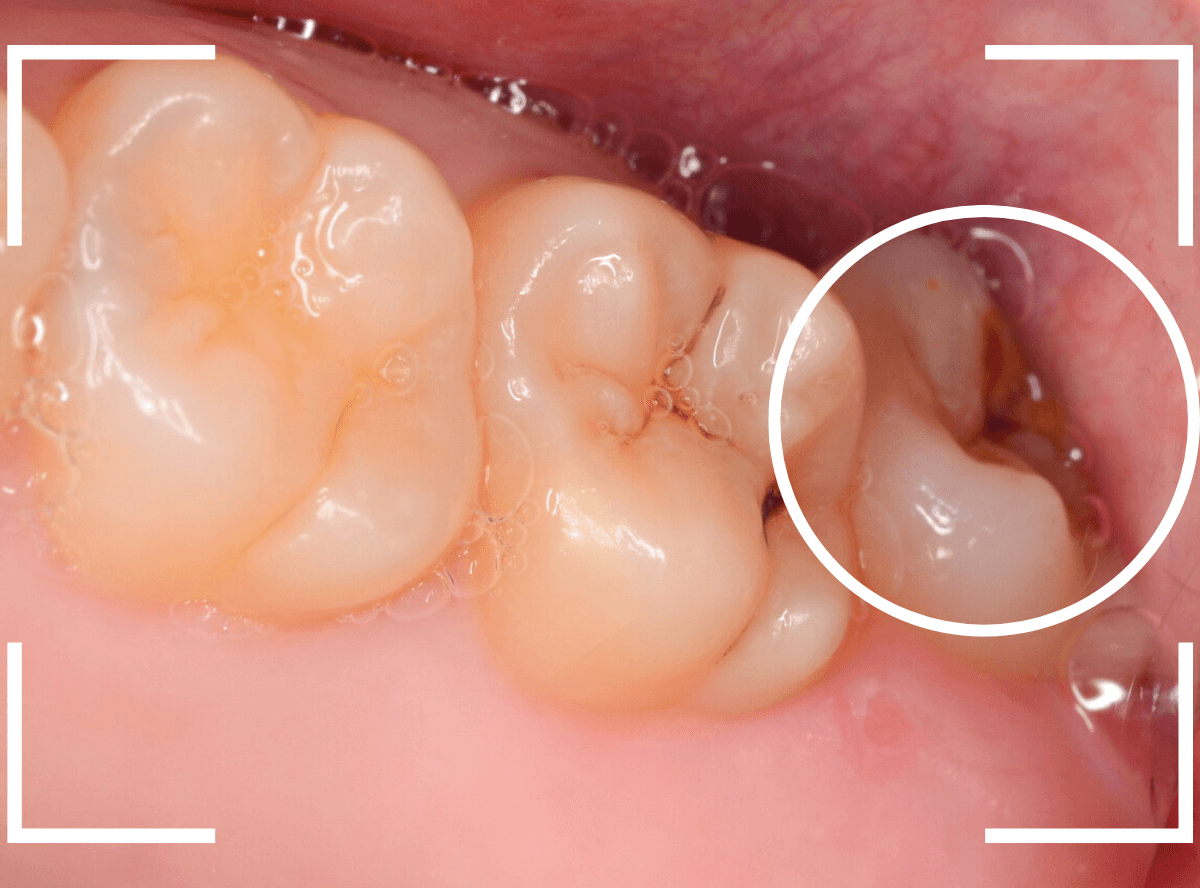

ここでは、比較的簡単なおやしらずの抜歯の例を中心にご紹介します。

このようなおやしらず、あなたはありませんか?